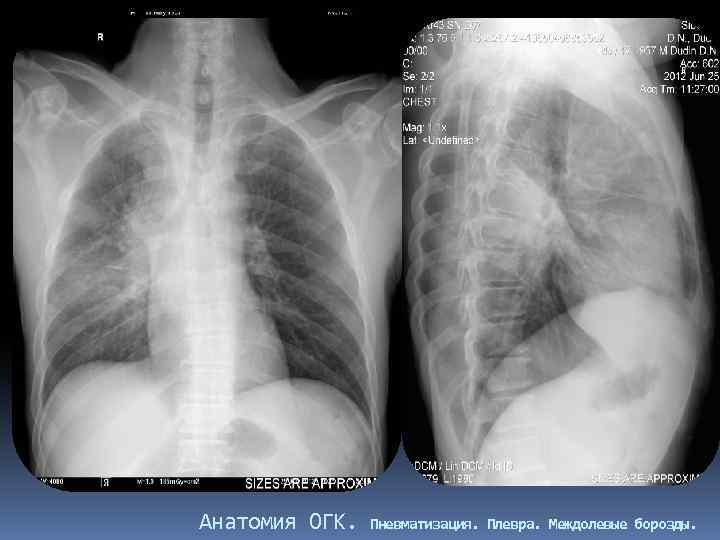

Анатомия ОГК. Пневматизация. Плевра. Междолевые борозды.

Междолевые борозды. Борозда между нижней и верхней, средней долями справа и верхней и нижней долями слева - главная междолевая борозда, имеется с обеих сторон. Справа между верхней и средней долями расположена дополнительная, малая горизонтальная междолевая борозда. Борозды бывают неполными, могут встречаться дополнительные борозды, образующие доли. Борозда состоит из двух слоев плевры, между которыми имеется потенциальная щель. В месте перехода грудной стенки в диафрагму, слои плевры образуют острый угол – синус (заворот): реберно диафрагмальный, реберно – медиастинальный. Задние реберно-диафрагмальные синусы самые глубокие, вытянуты в каудальном направлении.